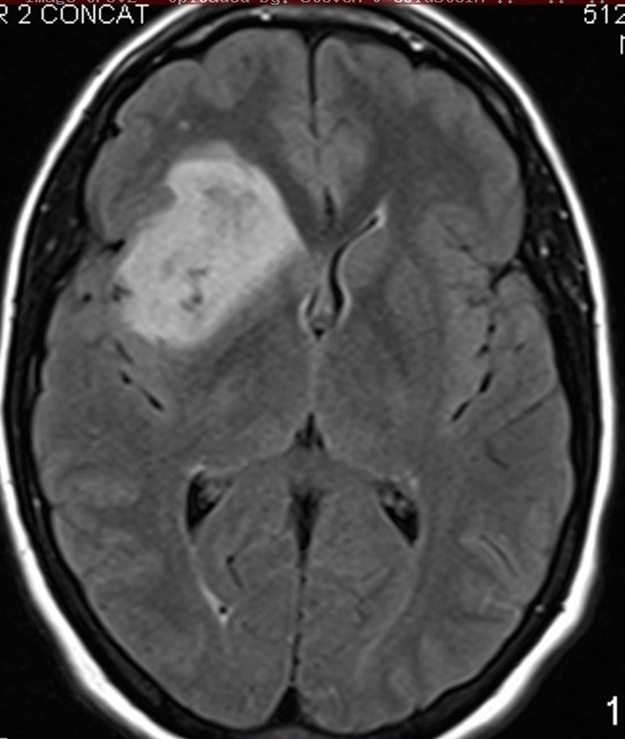

Peak incidence 50-60 years

Neoplasm occupies both hemispheres through the corpus callosum

Irregular ring enhancing

Average 1 year survival

GBM

astrocytoma who grade 4

ring enhancing T1

crosses corpus callosum

necrosis in the middle

(This pattern could be GBM, abccess with correct picture of infection ,or primary CNS lymphoma, but most likely GBM)

Butterfly lesion

astrocytoma grade 4